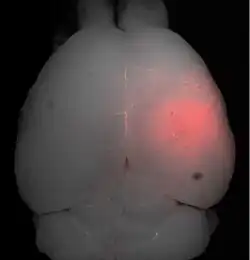

Die Blut-Hirn-Schranke lässt sich durch fokussierten Ultraschall öffnen. Dieser Effekt wurde erstmals 1956 nachgewiesen. Die Öffnung der Blut-Hirn-Schranke konnte durch die Anfärbung des Gehirns mit Trypanblau – einem Vitalfarbstoff, der normalerweise die Blut-Hirn-Schranke nicht passieren kann – und durch radioaktiv markiertes Phosphat nachgewiesen werden. Mikroskopisch konnten keine Veränderungen am Endothel beobachtet werden. Die Anwendung des Ultraschalls führte allerdings zu Hirnverletzungen.[137] 1960 wurde dann erstmals die Blut-Hirn-Schranke mit nur einer geringen Schädigung des umliegenden Parenchyms durch Ultraschall geöffnet.[138] Alle diese Versuche wurden mit hochintensivem fokussiertem Ultraschall, mit Leistungen im Bereich von 4000 Watt/cm², durchgeführt. Dabei entstehen Kavitationsblasen, die das Gewebe irreversibel zerstören können.[6]

- Fokussierender Ultraschall mit Mikrobläschen

Die Öffnung der Blut-Hirn-Schranke mit Ultraschall und gleichzeitig applizierten Mikrobläschen (Microbubbles) kam 2001 zum ersten Mal zur Anwendung.[139] Der Ansatz dabei ist, dass keine Kavitationsblasen generiert werden müssen, sondern injizierte Mikrobläschen die Funktion der sonst durch die hohe Ultraschallleistung erzeugten Kavitationsblasen übernehmen. Dadurch kann die Leistung des Ultraschalls deutlich reduziert werden; es besteht keine Gefahr mehr den behandelten Schädel, beziehungsweise das umliegende Gewebe, zu überhitzen. Die Technik ist mittlerweile so weit entwickelt, dass bei der Öffnung der Blut-Hirn-Schranke keine Apoptose, keine Ischämie oder sonstige Langzeitschädigung im Gehirn nachzuweisen sind. Wenige Stunden nach der Behandlung ist der alte Zustand der Blut-Hirn-Schranke wiederhergestellt.[6]

Der Fokus des Ultraschalls kann auf beliebige Areale im Gehirn gerichtet werden. Dadurch kann die Blut-Hirn-Schranke selektiv, auf bestimmte Hirnareale begrenzt, geöffnet werden. So können applizierte Wirkstoffe gezielt in diese Areale diffundieren.[140] Die behandelten Areale lassen sich durch eine simultan laufende Magnetresonanztomographie (MRT) genau verfolgen. Dabei dringt das für die MRT verwendete Kontrastmittel, beispielsweise Gadopentetat-Dimeglumin, nur durch die geöffneten Areale der Blut-Hirn-Schranke in das Gehirn ein. Diese Bereiche werden dadurch im MRT deutlich sichtbar hervorgehoben. Das hochpolare Gadopentetat-Dimeglumin ist nicht in der Lage die ungeöffneten Bereiche der Blut-Hirn-Schranke zu passieren.

Im Tiermodell Maus werden bei der Anwendung von fokussiertem Ultraschall mit Mikrobläschen Frequenzen im Bereich von 0,5 und 2 MHz[141] mit kurzen Pulslängen im Millisekundenbereich und Wiederholfrequenzen im Bereich von 1 Hz, über einen Zeitraum von weniger als einer Minute angewendet.[142] Der optimale Frequenzbereich liegt unterhalb von 1 MHz.[143] Die akustische Leistung beträgt weniger als ein Watt. Die verwendeten Mikrobläschen sind meist zugelassene Kontrastmittel aus der kontrastmittelverstärkten Sonographie. Sie haben typischerweise einen Durchmesser von 3 bis 4,5 µm, bestehen beispielsweise aus Humanalbumin und sind mit Perfluorpropan oder ähnlichen Schwergasen gefüllt.[144]